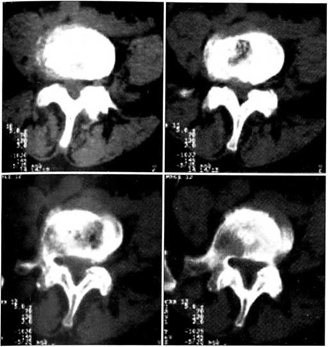

Всем больным проводилось лучевое обследование, включавшее рентгенографию позвоночника в двух проекциях (при поясничной боли дополнительно выполнялись функциональные пробы), в сомнительных случаях для исключения дискорадикулярного конфликта назначалась магнитно-резонансная или компьютерная (предпочтительнее) томография пораженного отдела (рис. 2). У 13 больных была выявлена нестабильность сегментов L5~S1 и L4-5. На основании результатов клинического и рентгенологического обследования установлено, что причиной болевого синдрома у рассматриваемой группы пациентов являлись дегенеративные изменения в межпозвонковых суставах, т.е. диагноз формулировался как спондилоартроз определенных сегментов (в грудном отделе чаще были поражены сегменты от ТЗ до Т12, в поясничном отделе — L3-4, L4~5, L5-S1).

Рис. 2. Деформирующий артроз дугоотростчатых суставов поясничных позвоночных сегментов по данным КТ.